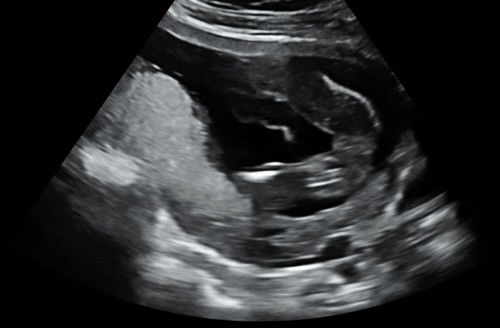

SCAN 35WEEKS

Hi mommyy , boleh ke kalau nak scan lagi kandungan 35week🤭 scan saja untuk tengok baby kita ada yang pernah tak scan 35weeks share pengalaman sikit 😝

PINJAM MATA IBU IBU DILUAR 🥺

Hi nak tanya mummy dekat luar nampak girl ke boy 😍🤭 #firsttime_mommy